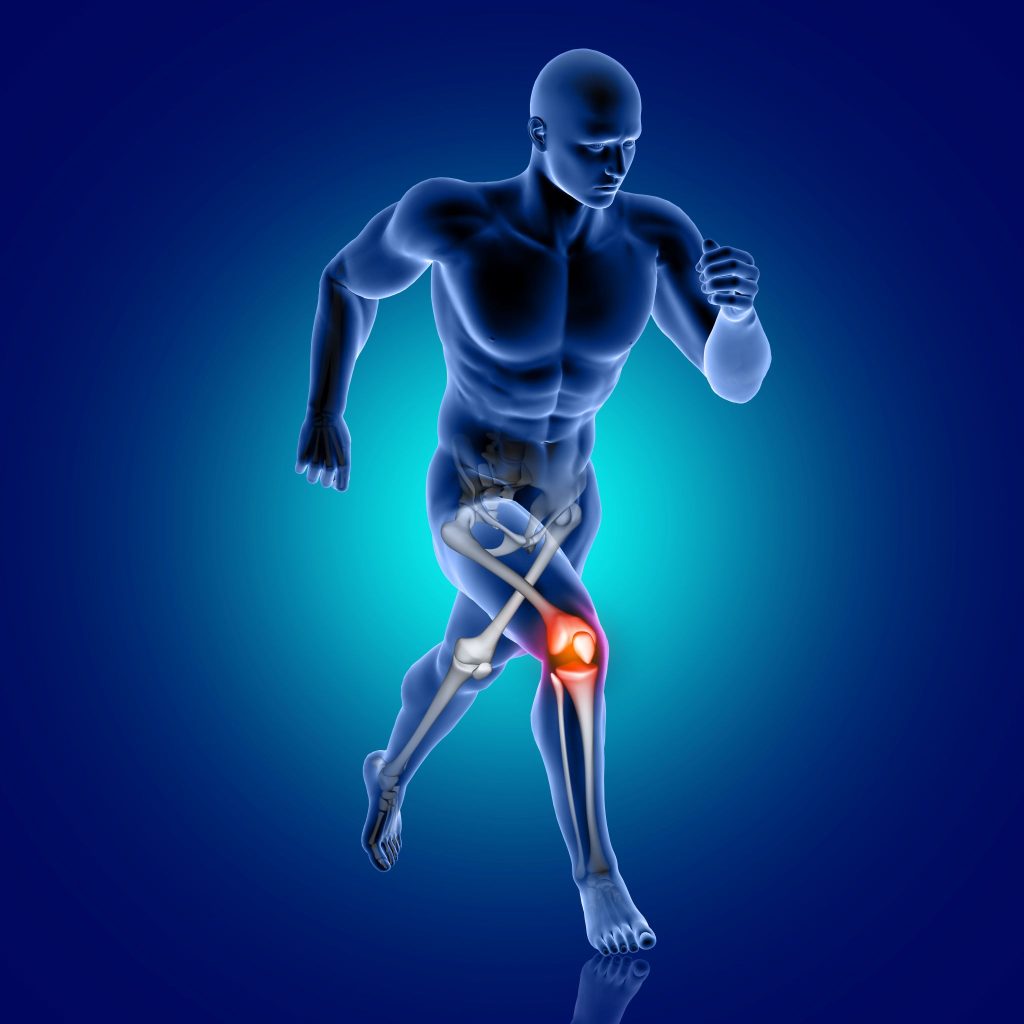

Bạn vừa chơi thể thao, một động tác xoay người đột ngột hoặc va chạm khiến đầu gối phát ra tiếng rắc khi chấn thương, sau đó bạn cảm thấy đầu gối lỏng gối bất thường, sưng phù nhanh chóng trong vài giờ. Đây có thể là dấu hiệu của tổn thương dây chằng chéo – một trong những chấn thương khớp gối nghiêm trọng nhất. Hiểu rõ các mức độ đứt dây chằng và được chẩn đoán sớm giúp lựa chọn phương pháp điều trị phù hợp, tránh biến chứng lỏng gối mạn tính và thoái hóa khớp về sau.

Dây chằng chéo trước (ACL) là một trong những dây chằng quan trọng nhất của khớp gối, có chức năng ổn định khớp, ngăn cản xương chày trượt ra trước quá mức và hỗ trợ xoay khớp an toàn. Đứt dây chằng chéo thường xảy ra ở người chơi thể thao (bóng đá, bóng rổ, cầu lông) với các cơ chế phổ biến: xoay người đột ngột khi chân cố định, tiếp đất sai tư thế, hoặc va chạm trực tiếp vào đầu gối.

Các mức độ đứt dây chằng chéo

Dựa vào mức độ tổn thương, đứt dây chằng chéo được phân thành 3 cấp độ: